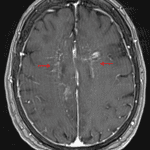

MRI

- Relatively symmetric T2/FLAIR signal hyperintensity most pronounced in the supratentorial deep gray nuclei and deep white matter, including the internal capsules and corpus callosum, with associated curvilinear and nodular enhancement in a perivascular distribution

- Patchy corresponding restricted diffusion

- No midline shift or evidence of herniation or hydrocephalus